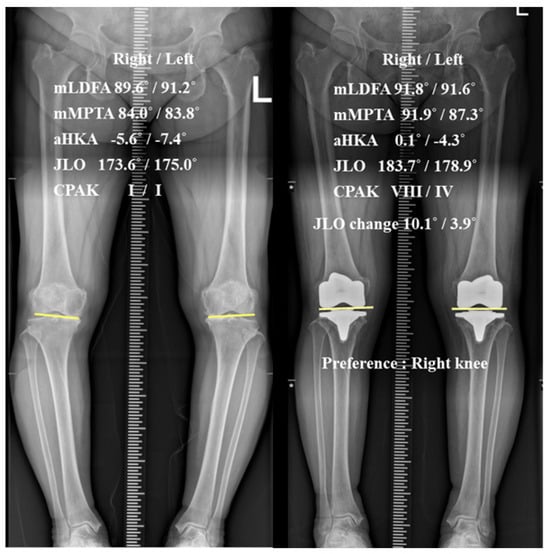

The Degree of Joint Line Obliquity Change Is Not Associated with Patient Preference in Bilateral Posterior-Stabilized Total Knee Arthroplasties

Objectives: To evaluate patient reference in paired bilateral posterior stabilized (PS) total knee arthroplasties (TKAs) with significantly different degrees of joint line obliquity (JLO) change. Methods: A retrospective review was conducted on 128 patients who underwent paired bilateral PS TKAs, with greater and [...] Read more.

Objectives: To evaluate patient reference in paired bilateral posterior stabilized (PS) total knee arthroplasties (TKAs) with significantly different degrees of joint line obliquity (JLO) change. Methods: A retrospective review was conducted on 128 patients who underwent paired bilateral PS TKAs, with greater and smaller JLO changes (G-ΔJLO and S-ΔJLO knees; a side-to-side difference in JLO change >3° between G-ΔJLO and S-ΔJLO knees). The mean follow-up period was 3.9 years (minimum 2 years). Radiographic changes in JLO were measured according to the Coronal Plane Alignment of the Knee (CPAK) classification. Maintenance of the CPAK type and JLO direction (apex distal, neutral, and apex proximal) was investigated. Clinically, the preferred TKA out of greater and smaller JLO changes was investigated. The Hospital for Special Surgery and Western Ontario and McMaster Universities Osteoarthritis Index were evaluated. Results: The average JLO change was 10.5° in the G-ΔJLO knees and 5.5° in the S-ΔJLO knees (p < 0.001). The CPAK type and JLO direction was better maintained in the S-ΔJLO knees (p < 0.001, respectively). Regarding preference, 40 patients (31.2%) were satisfied with bilateral TKAs without a specific preference, while 44 patients (34.3%) preferred TKAs of the G-ΔJLO knee and 44 patients (34.3%) preferred the S-ΔJLO knee (p = 1.000). No significant differences were found in the patient reported outcomes between the G- and S-ΔJLO knees. Conclusions: The degree of joint line obliquity change was not associated with patient preference in bilateral PS TKAs. JLO preservation may not be a critical determinant of patient preference in PS TKA. Full article